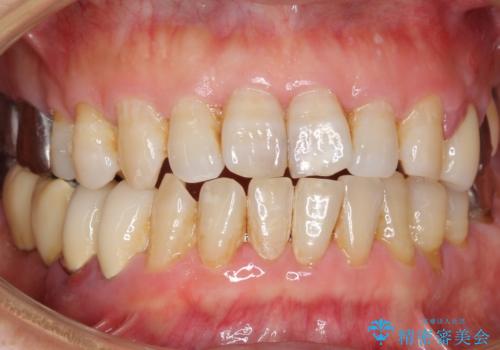

歯ぐきが腫れている 残せない歯を抜歯してブリッジへ 60代男性

- 左上の歯ぐきが腫れていることを主訴に来院された患者様です。

精査したところ、歯ぐきが腫れている左上の小臼歯(左上4)は保存不可能な状態でした。

自然な仕上がりと咬み心地に喜んで下さいました。

歯茎の腫れも治り、ご満足頂けました。